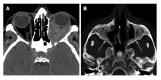

Orbital inflammatory disease (OID) represents a collection of inflammatory conditions affecting the orbit. OID is a diagnosis of exclusion, with the differential diagnosis including infection, systemic inflammatory conditions, and neoplasms, among other conditions. Inflammatory conditions in OID include dacryoadenitis, myositis, cellulitis, optic perineuritis, periscleritis, orbital apicitis, and a focal mass. Sclerosing orbital inflammation is a rare condition with a chronic, indolent course involving dense fibrosis and lymphocytic infiltrate. Previously thought to be along the spectrum of OID, it is now considered a distinct pathologic entity. Imaging plays an important role in elucidating any underlying etiology behind orbital inflammation and is critical for ruling out other conditions prior to a definitive diagnosis of OID. In this review, we will explore the common sites of involvement by OID and discuss differential diagnosis by site and key imaging findings for each condition.